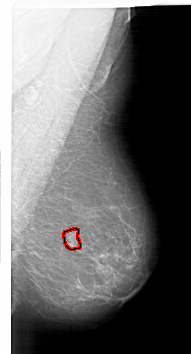

A_1718_1.RIGHT_MLO

RIGHT_CC LINES 6481 PIXELS_PER_LINE 3346 BITS_PER_PIXEL 12 RESOLUTION 43.5 OVERLAY

RIGHT_MLO LINES 6016 PIXELS_PER_LINE 3241 BITS_PER_PIXEL 12 RESOLUTION 43.5 OVERLAY

FILE: A_1718_1.RIGHT_MLO.OVERLAY

TOTAL_ABNORMALITIES 1

ABNORMALITY 1

LESION_TYPE MASS SHAPE FOCAL_ASYMMETRIC_DENSITY MARGINS ILL_DEFINED

ASSESSMENT 4

SUBTLETY 4

PATHOLOGY BENIGN

TOTAL_OUTLINES 1

BOUNDARY

FILE: A_1718_1.RIGHT_CC.OVERLAY